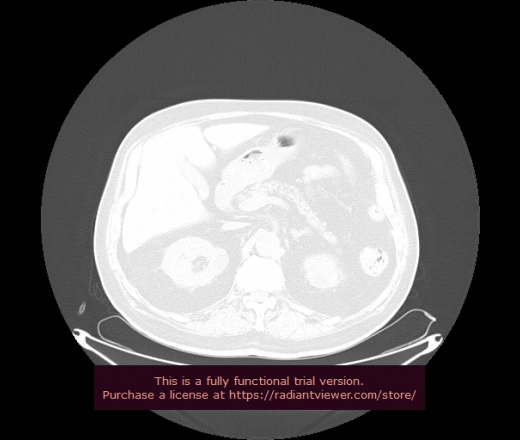

Уважаемые коллеги, если имеется интерес, сможете ли Вы спрогнозировать дальнейшее +-одинаковое течение процесса у 4 данных разных пациентов? Зацепиться где-то можно очень просто, где-то нельзя.